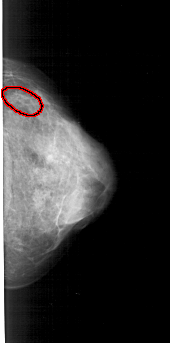

A_1570_1.RIGHT_CC

RIGHT_CC LINES 4801 PIXELS_PER_LINE 2371 BITS_PER_PIXEL 12 RESOLUTION 43.5 OVERLAY

FILE: A_1570_1.RIGHT_CC.OVERLAY

TOTAL_ABNORMALITIES 1

ABNORMALITY 1

LESION_TYPE CALCIFICATION TYPE PLEOMORPHIC DISTRIBUTION CLUSTERED

ASSESSMENT 4

SUBTLETY 1

PATHOLOGY MALIGNANT

TOTAL_OUTLINES 1

BOUNDARY